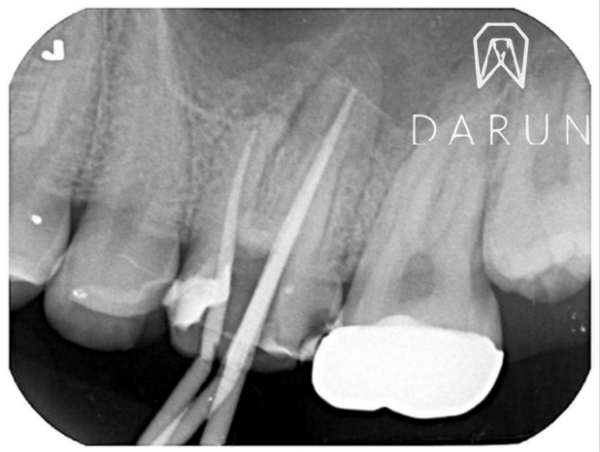

레진으로 덮여있던 곳을 조심스레 다 제거했더니,

이제 신경치료 흔적들이 나오기 시작합니다.

왜 검냐구요?

Contamination 된 것들은

갈색 혹은 검은색을 띄게됩니다.

이제 신경뿌리 관따라서

오염 된 것들을 전부다 제거해야 합니다.

조금씩 제거할때마다,,

이렇게 오염물질이 계속 나옵니다.

왜 안팠는지,, 신기하죠?

이런것들은 언 제든지 컨디션 조금만 나빠지면

확 붓거나 터질 수 있어요.

얼른 치료 받으셔야 돼요.